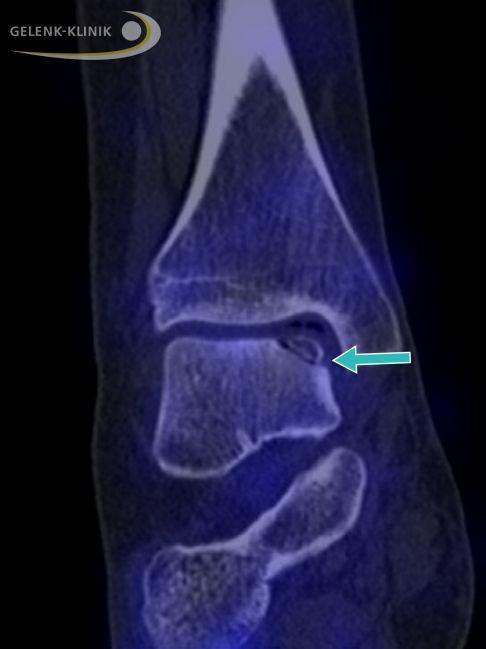

Distorsion (Verdrehung oder Umknicken) des Sprunggelenks verursachen können komplexe Schäden im Knorpelgewebe und im Knochengewebe des oberen Sprunggelenks (OSG) zur Folge haben. Diese komplexen Knochen-Knorpelschäden werden auch als Osteochondrose bzw. Osteochondrosis dissecans (OD) im Sprunggelenk bezeichnet. Aus einer osteochondralen Läsion kann langfristig eine schmerzhafte Arthrose im Sprunggelenk entstehen. Deshalb stellt sich ganz besonders bei jungen Patienten die Frage, wie diese bestmöglich behandelt werden kann.

In einem fortgeschrittenen Stadium der Osteochondrosis dissecans (III-V mit partieller Lösung des Knochenherdes bis hin zur Zystenbildung) sind die gängigen Verfahren mit Anbohrung des Knochens und Mikrofrakturierung nach Abschluss des Knochenwachstums nicht mehr ausreichend.

Für diese Fälle steht die Knorpel-Knochentransplantation, kurz OATS für osteochondrale autologe Transplantation, am Sprunggelenk zur Verfügung.